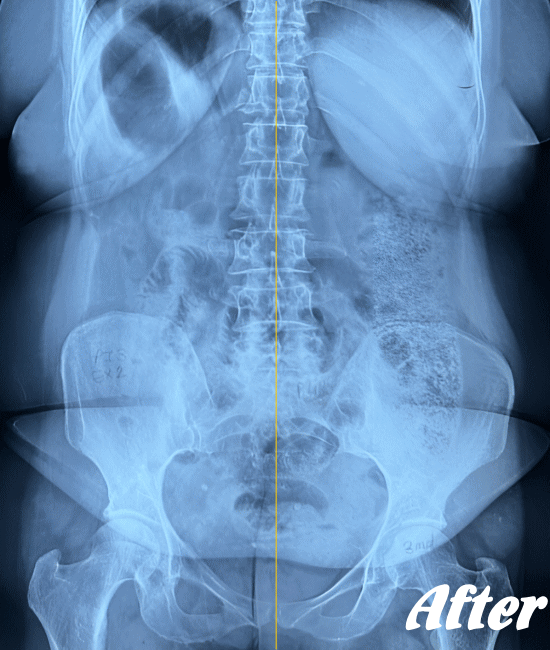

レントゲン、CT、MRIといった画像診断などで坐骨神経痛の原因となる病気(例えば、ヘルニアや脊柱管狭窄症など)が見つかれば、その治療を行います。原因となる病気が見つからない場合は、第一選択肢として、保存療法が適応されます。

HALOカイロプラクティック☆平和島整体院では、仙腸関節や腰、股関節などの部位を解剖学的に正しい状態へ戻すことで、筋肉をゆるめ、関節の詰まりを広げ、圧迫されてしまった神経を解放し、痛みや痺れのない状態へと回復させます。

また、首(頚椎)の歪みにより腰に負担がかかることで坐骨神経痛を発症することもあるため、首も調整します。

ただし、歩行に支障をきたすような激しい痛みの場合は、「股関節のズレが酷い」「腰椎の椎間が詰まっている」「ヘルニアが突出している」「仙腸関節が炎症を起こしている」…等々、通常よりも症状が悪化しているため施術回数が長引くことをご理解いただいたうえで、当院へお越し下さい。